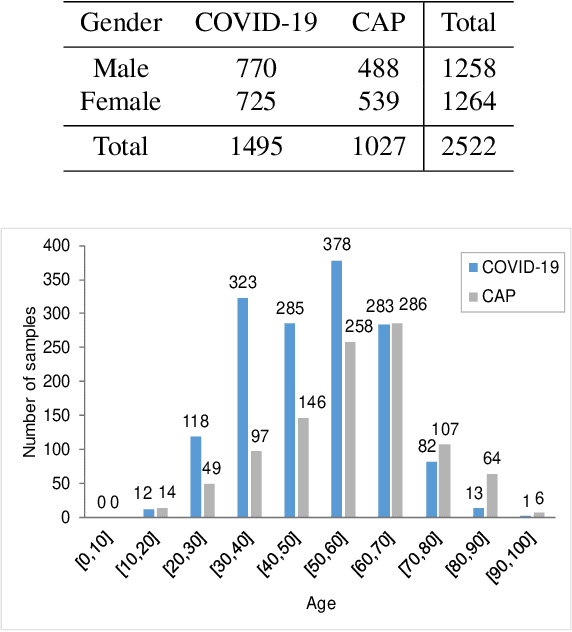

Recently, the outbreak of Coronavirus Disease 2019 (COVID-19) has spread rapidly across the world. Due to the large number of affected patients and heavy labor for doctors, computer-aided diagnosis with machine learning algorithm is urgently needed, and could largely reduce the efforts of clinicians and accelerate the diagnosis process. Chest computed tomography (CT) has been recognized as an informative tool for diagnosis of the disease. In this study, we propose to conduct the diagnosis of COVID-19 with a series of features extracted from CT images. To fully explore multiple features describing CT images from different views, a unified latent representation is learned which can completely encode information from different aspects of features and is endowed with promising class structure for separability. Specifically, the completeness is guaranteed with a group of backward neural networks (each for one type of features), while by using class labels the representation is enforced to be compact within COVID-19/community-acquired pneumonia (CAP) and also a large margin is guaranteed between different types of pneumonia. In this way, our model can well avoid overfitting compared to the case of directly projecting highdimensional features into classes. Extensive experimental results show that the proposed method outperforms all comparison methods, and rather stable performances are observed when varying the numbers of training data.